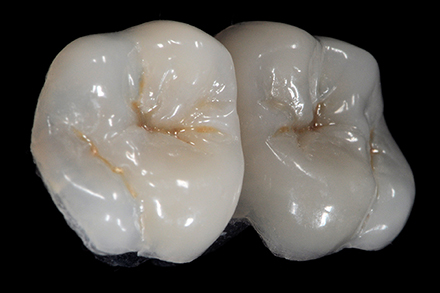

Composite overlay (made with VITA VM LC) on the model.

Occlusal anatomy